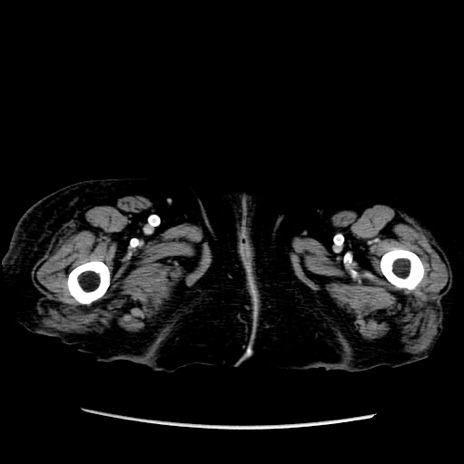

症例14(横断像)

【症例】 90歳代女性

【主訴】 腹痛・嘔吐

【現病歴】今朝から左側腹部痛を認めた。 経過観察していたが、嘔吐を認めたため来院。

【既往歴】 子宮癌術後

【身体所見】 意識清明、BP 127/54mmHg、P 98bpm Sp02 95%(RA)、BT 35.8°C、腹部平坦・軟腸ぜん動音聴取良好、右下腹部圧痛(+) 反跳痛なし

【データ】WBC 9800、CRP 0.46